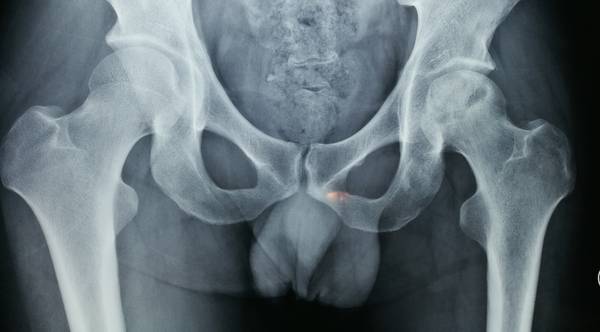

股骨头坏死

死骨刮除扩髓

骨科机器人辅助定位

股骨头坏死骨刮除

松质骨,人工骨混合植入

游离腓骨段植入

吻合血管重建血运